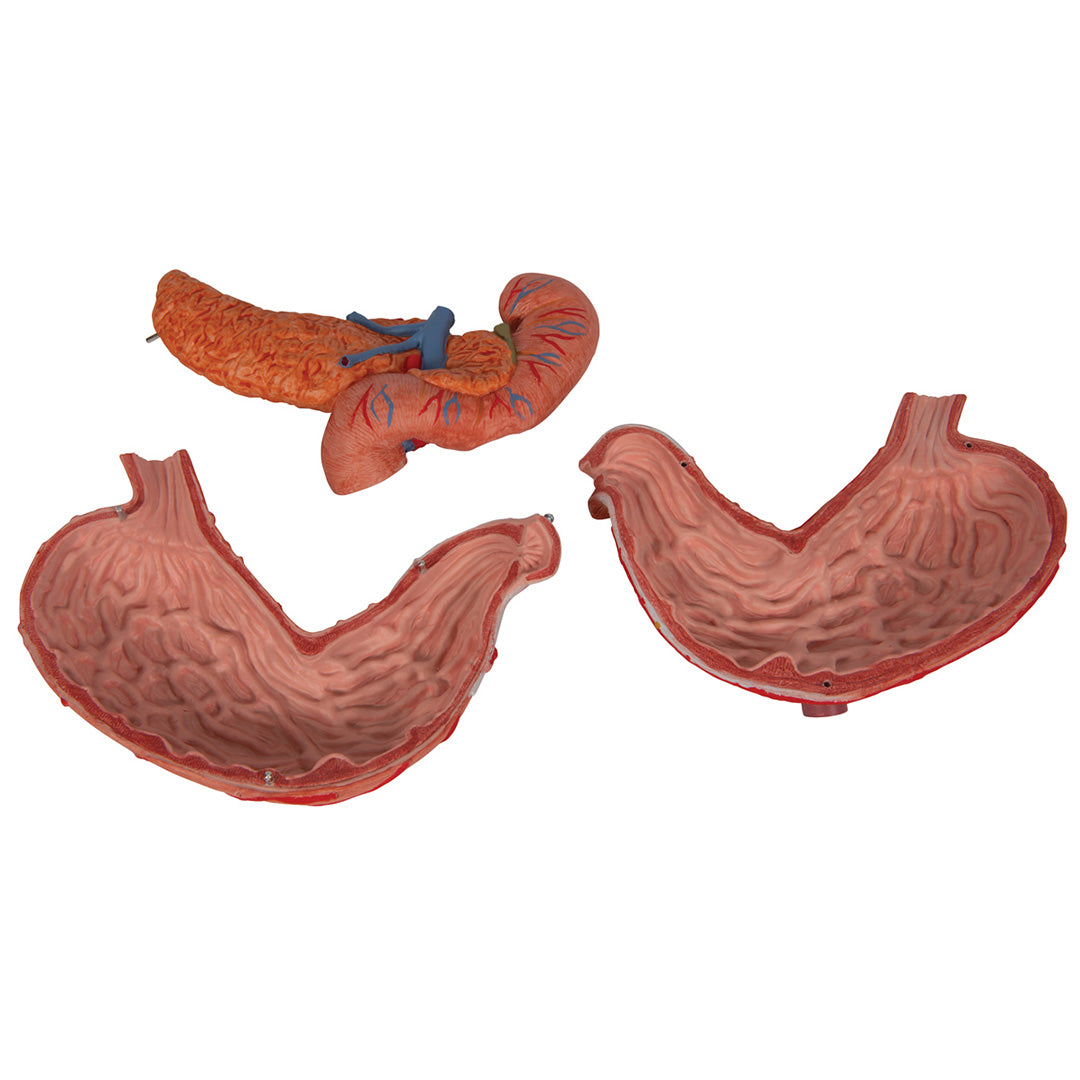

Estómago, en 3 piezas

Estómago, en 3 piezas

El modelo presenta las capas de la pared del estómago desde la cardia hasta el píloro.

La mitad delantera del estómago se puede retirar.

Se presentan:

• Parte inferior del esófago

• Conductos

• Nervios

• Duodeno

• Páncreas

Con soporte.

Peso 0.87 kg.

Dimension 25 x 22 x 12 cm